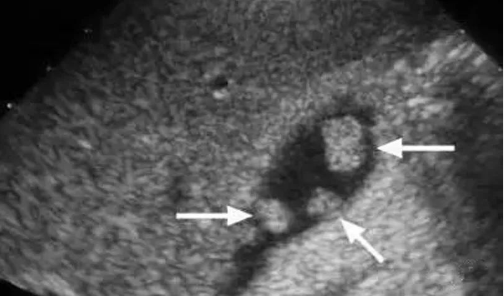

大的结石堵在胆囊出口,小一点的堵在胆总管,那么更小的呢?这样的结石称为“泥沙样结石”,超声下可发现,它们可以顺利达到胆总管的开口,而胆总管的开口在十二指肠,旁边紧挨着的就是胰腺管道胰管的开口,于是,接下来这些很小的结石可以更加顺利地进入胰管,诱发“胆源性胰腺炎”。

一些患者虽然没有过胆囊炎发作,但是胆囊里已经全是结石(充满型结石),胆汁很少或几乎没有;或是由于胆囊壁过度增生增厚,导致胆囊腔几乎消失(胆囊腺肌症)。